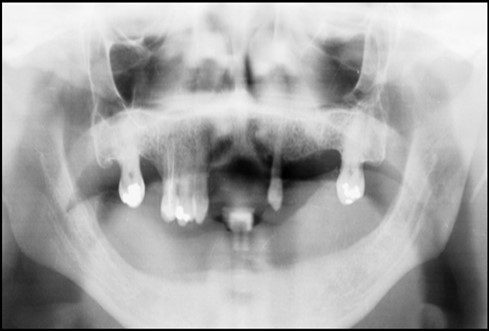

Post operatively after 3 months, osseointegration was evaluated clinically and radiographically (Figure 5a,b) and the implants were well prepared to receive the prosthesis. The second stage surgery was performed in which cover screws were removed and healing abutment were inserted into the implants (Figure 6). After a time period of two weeks, peri-implant soft tissue healing was examined, and existing denture was relined after relieving at the abutment site. Later, the healing abutment is removed using a 1.25 mm hex driver. Internal portion of the implant is irrigated and dried to make sure if it is free of debris and soft tissue. A periodontal probe was used to measure the gingival cuff height at the right and left canine site of implant location. Selected ball abutment were placed onto each implant using 1.25 mm hex driver and 30 Ncm torque wrench (Figure 7A).

Figure 6.Panoramic radiograph after the insertion of two implants

Panoramic radiograph after the insertion of two                 implants